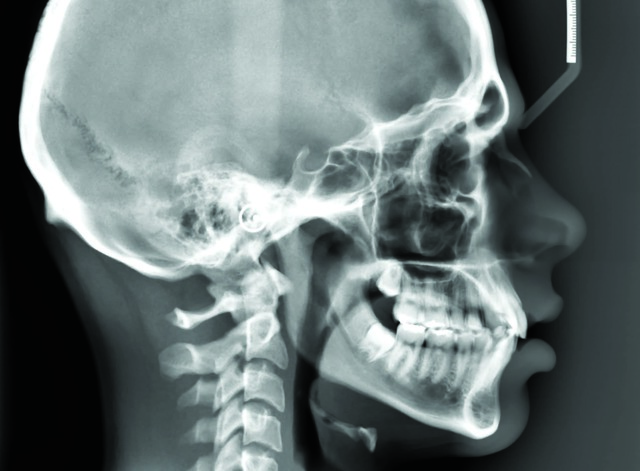

Odontologia radiologia

Primera Radiografía

El científico Roentgen obtuvo la primera radiografia de la mano de su esposa.